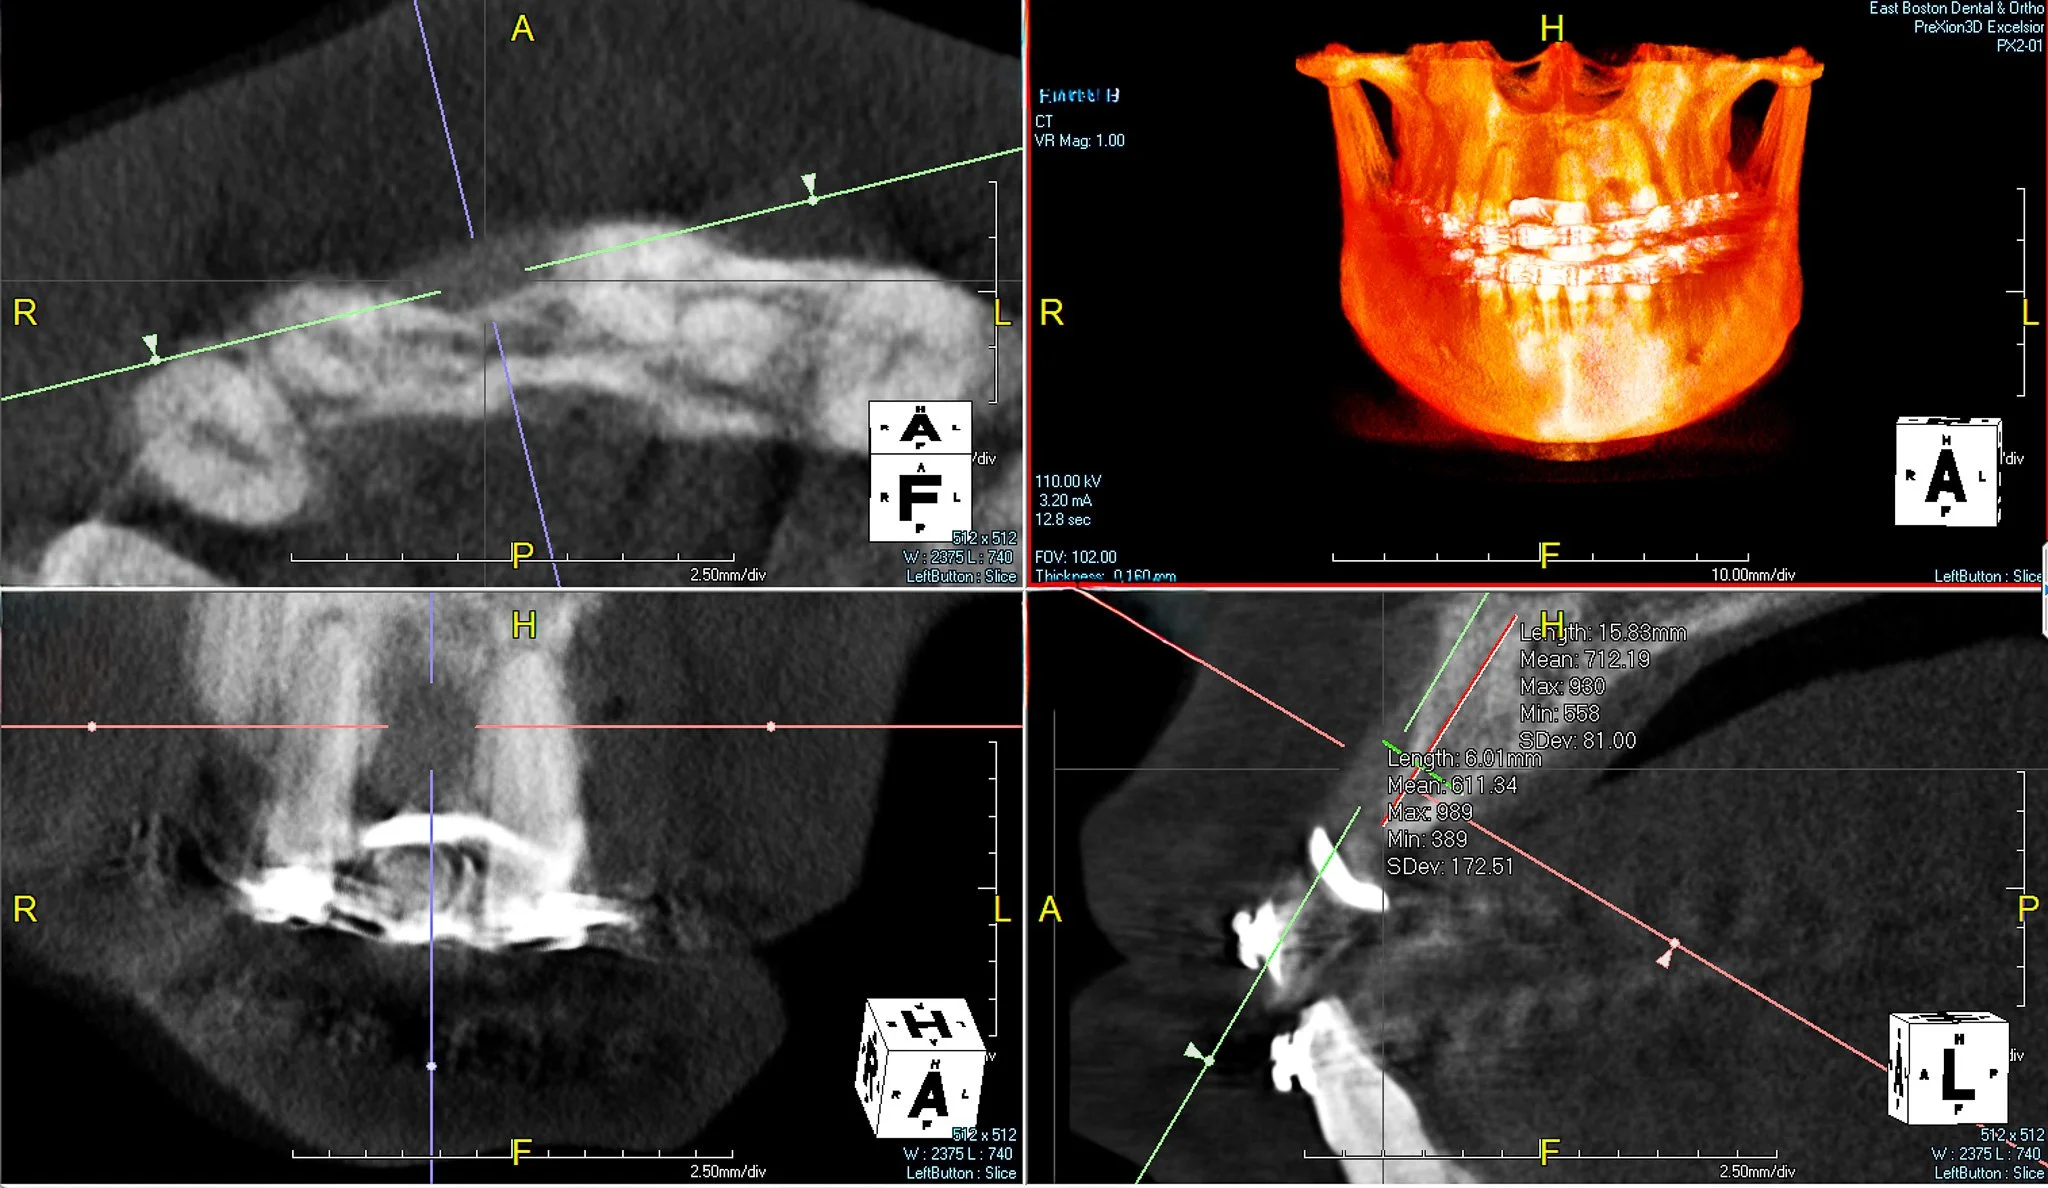

A 33 year-old male patient has been missing #8 for more than a decade due to physical trauma in the area. The patient had given treatment options of a bridge and a dental implant. After a thorough discussion among the patient, the restorative dentist, and me, we came to the conclusion that a dental implant will be a more optimal and definitive treatment for the patient.

As you can see, there is a buccal-palatal concavity from the axial view on #8. Thus, GBR was planned for horizontal ridge augmentation to address a significant buccal bone dehiscence.